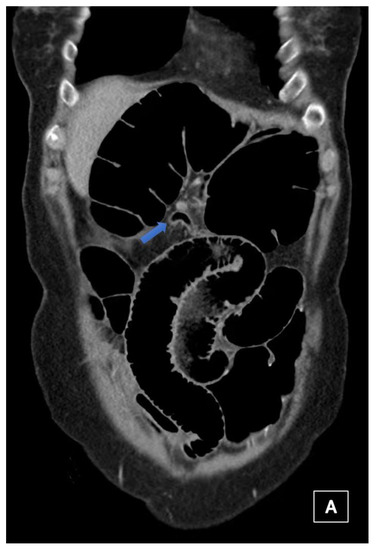

4.4.2. Computerised Tomography (CT) Scan

| Abdominal radiograph | 11 (68.75%) | Five patients had CT as the only imaging. |

| Non-specific bowel loops/SBO | 5 (46%) | |

| Classical single loop of large bowel | 6 (54%) | |

| CT Abdomen and pelvis | 15 | One patient operated without CT. |

| CV not described | 1 | |

| CV correctly identified | 14 (93.3%) | |

| Caecal diameter >10 cm | 10 (67%) | |

| Whirl sign | 12 (80%) | |

| Split-wall sign | 13 (86.6%) | |

| X-marks-the-spot sign | 14 (93.3%) | |

| Double transition point | 13 (86.6%) | |

| Ileocaecal twist | 13 (86.6%) | |

| Central appendix | 11 (73.3%) |